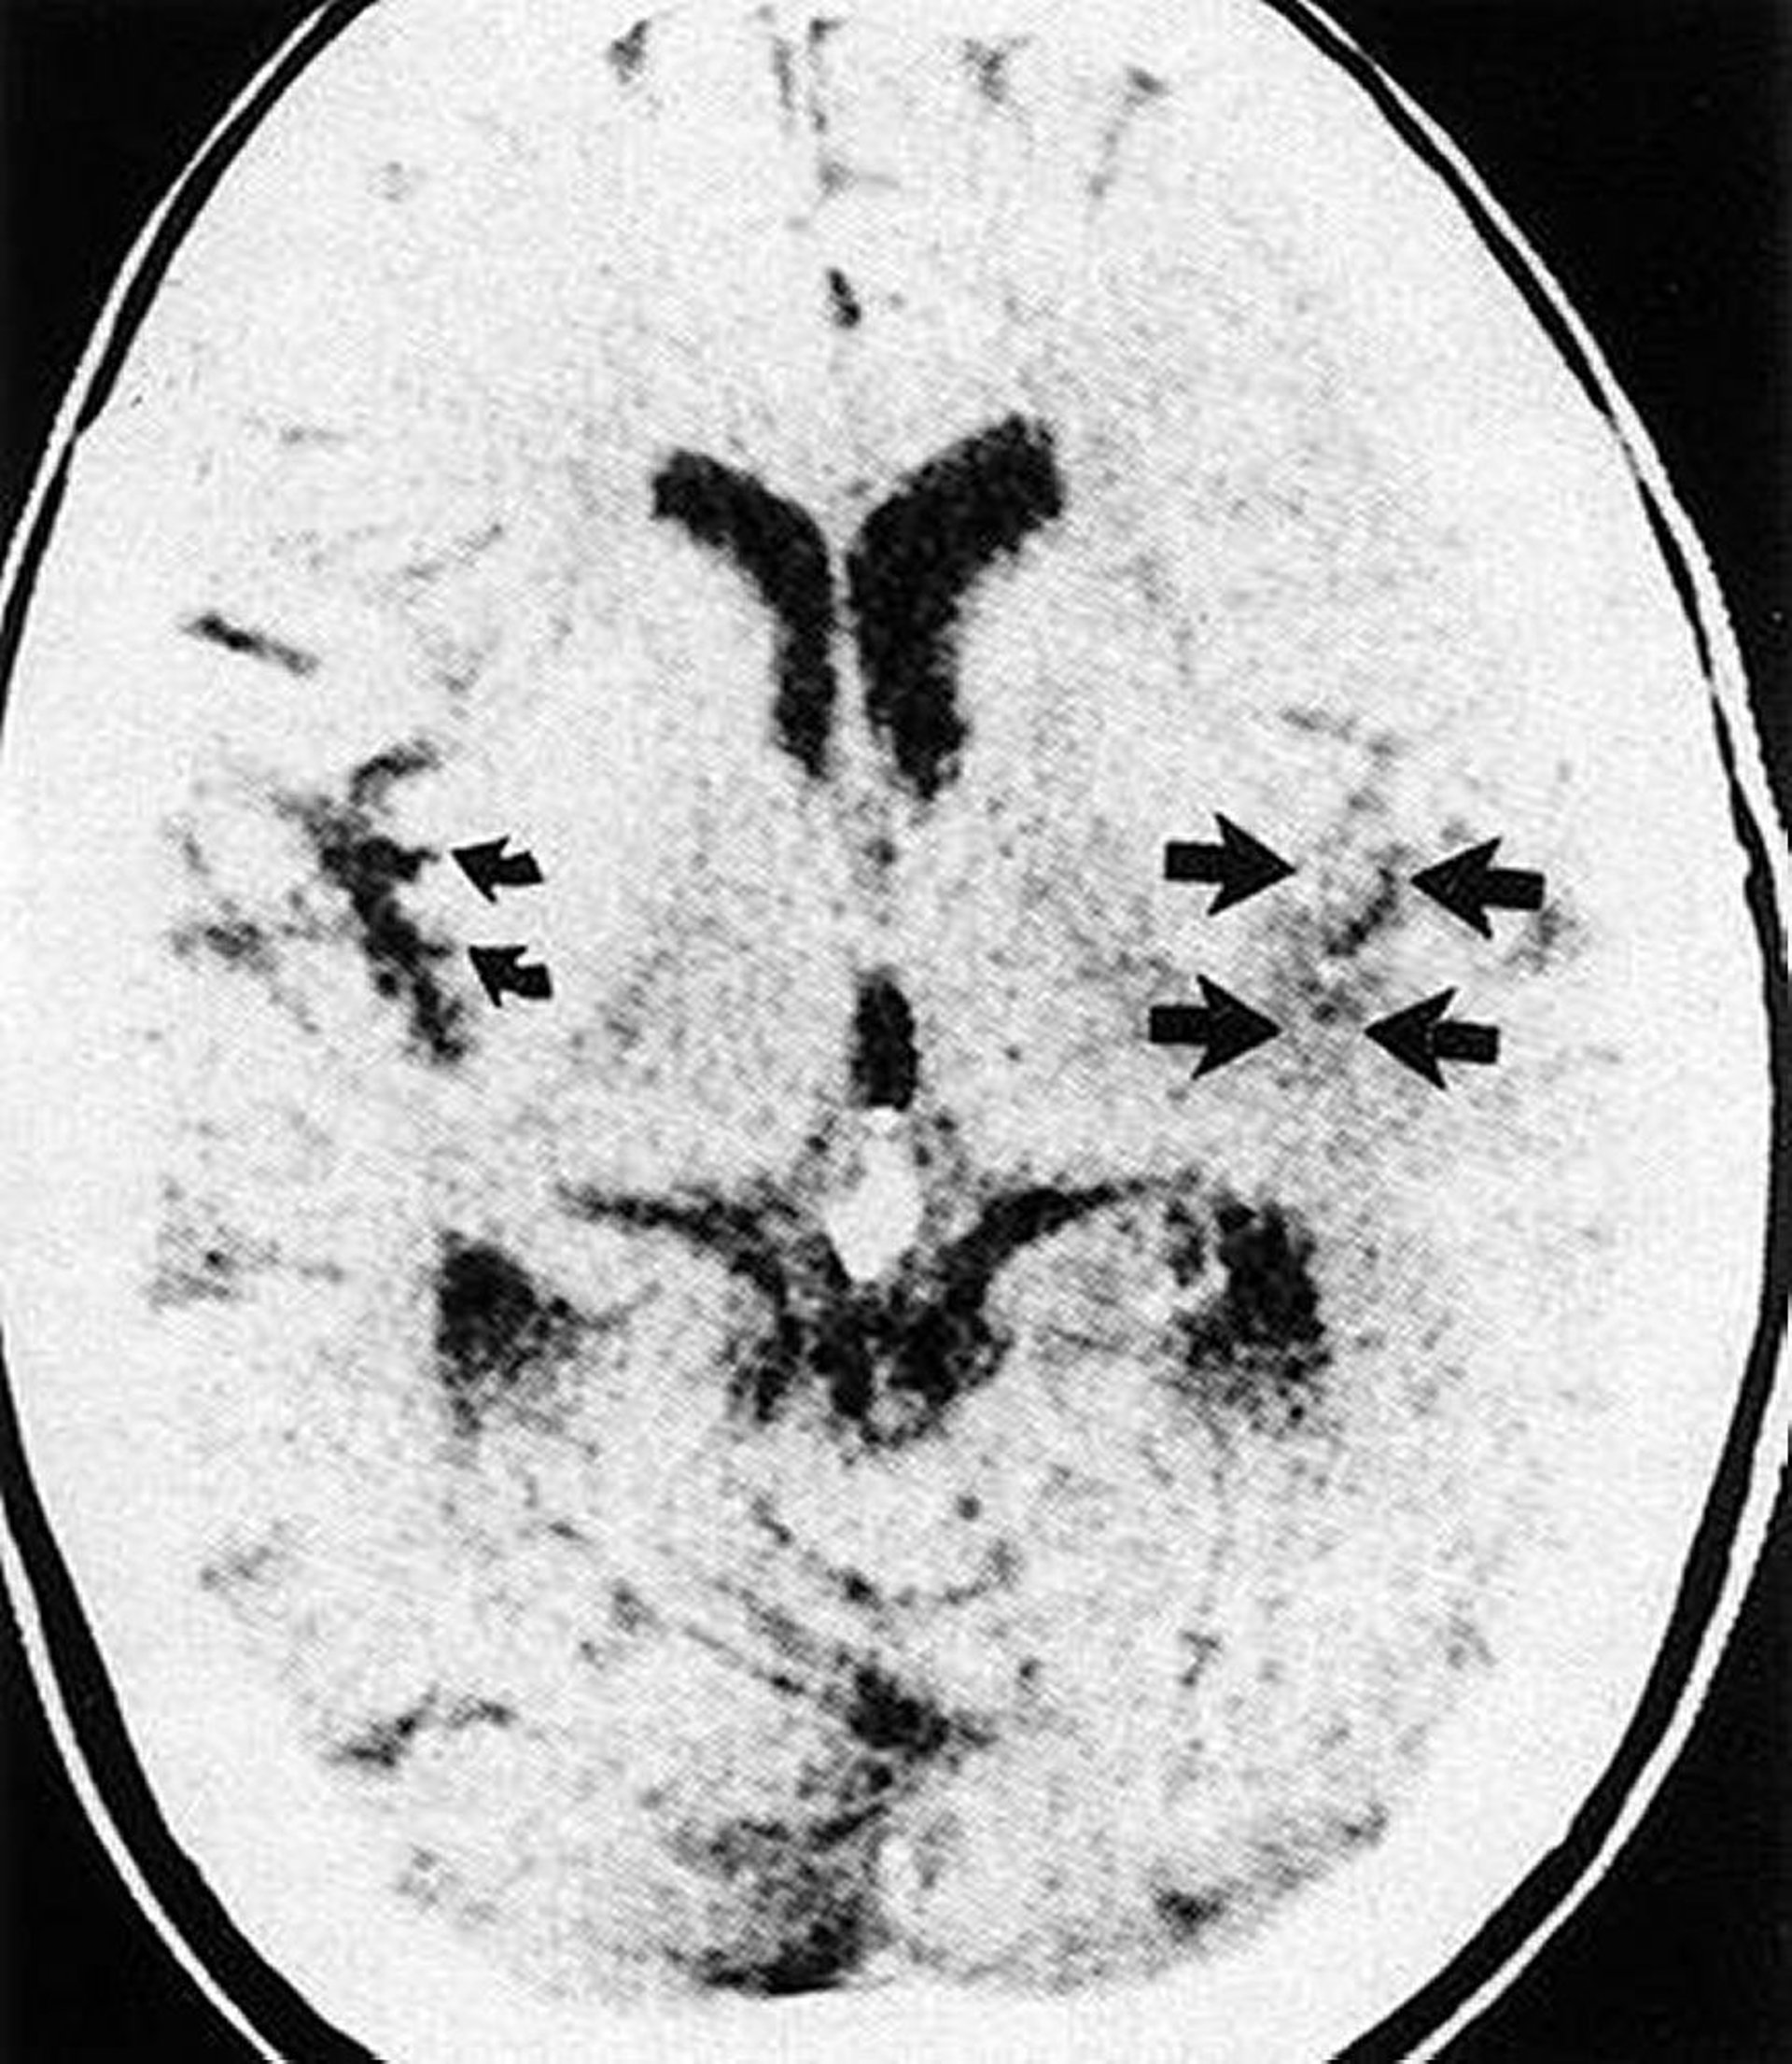

Insular Ribbon Loss

This CT scan shows effacement of the sylvian fissure and insular ribbon (straight arrows) on the infarcted side of brain compared with the normal insular ribbon (curved arrows).

By permission of the publisher. From Geremia G, Greenlee W. In Atlas of Cerebrovascular Disease. Edited by PB Gorelick and MA Sloan. Philadelphia, Current Medicine, 1996.